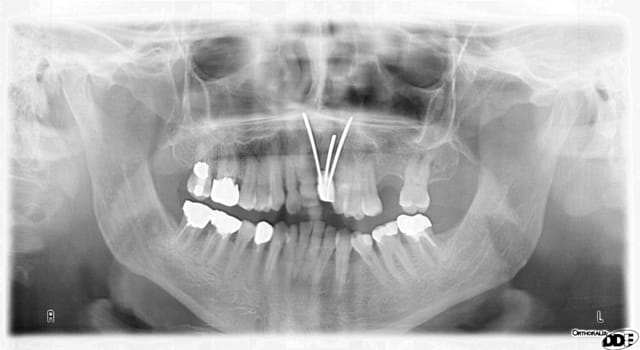

Patient de 33 ans venant pour une molaire douloureuse...

Je pense tenir le record du n'importe quoi implantaire.

Pourtant les endos ne sont pas immondes

Quand on dit que ça marche les implants courts !

euh 37 et 16 y a comme un problème